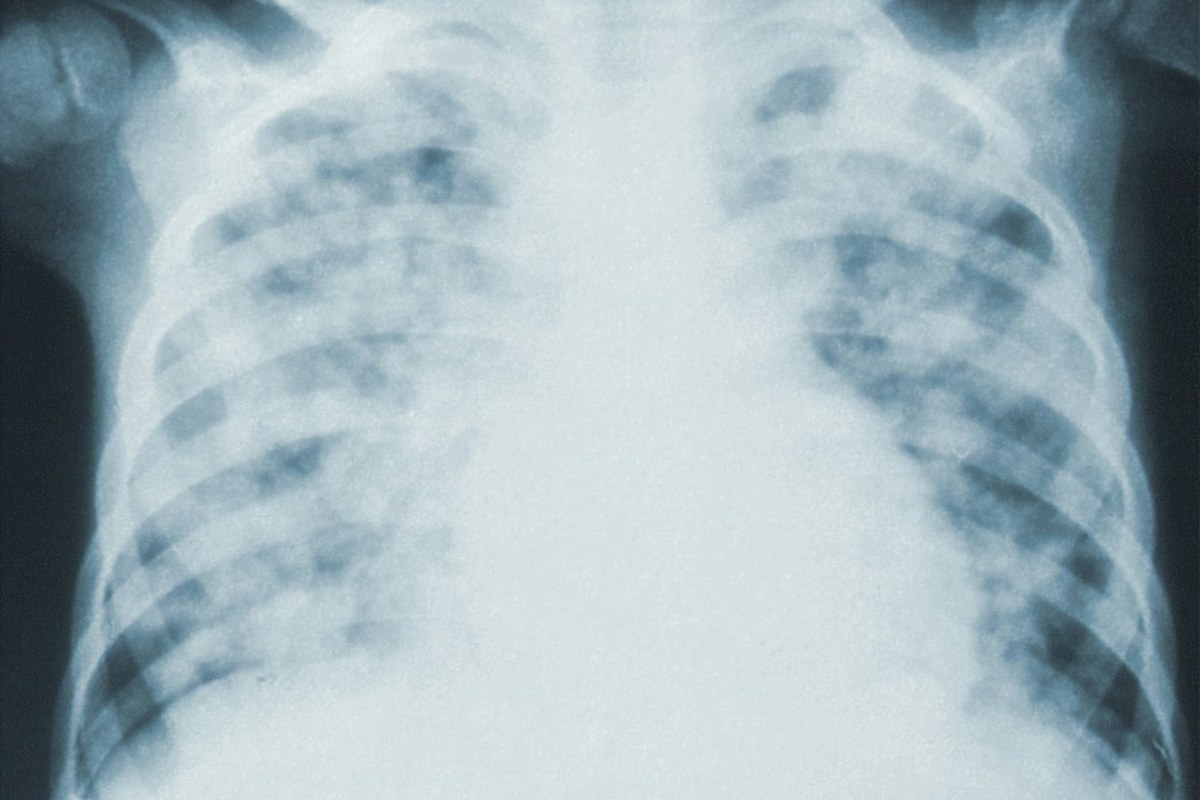

소세포폐암의 두 가지 병기

소세포폐암은 진행 정도에 따라 크게 두 단계로 나뉩니다.

| 제한병기 | 암이 한쪽 폐와 인접 림프절에 국한된 상태 | 약 30% |

| 확장병기 | 암이 폐 밖으로 퍼져나가거나 다른 장기로 전이된 상태 | 약 70% |

제한병기일 때 완치를 기대할 수 있으며, 방사선 치료 범위 내에 포함될 수 있습니다. 하지만 병이 진행되면 치료가 훨씬 어려워집니다.